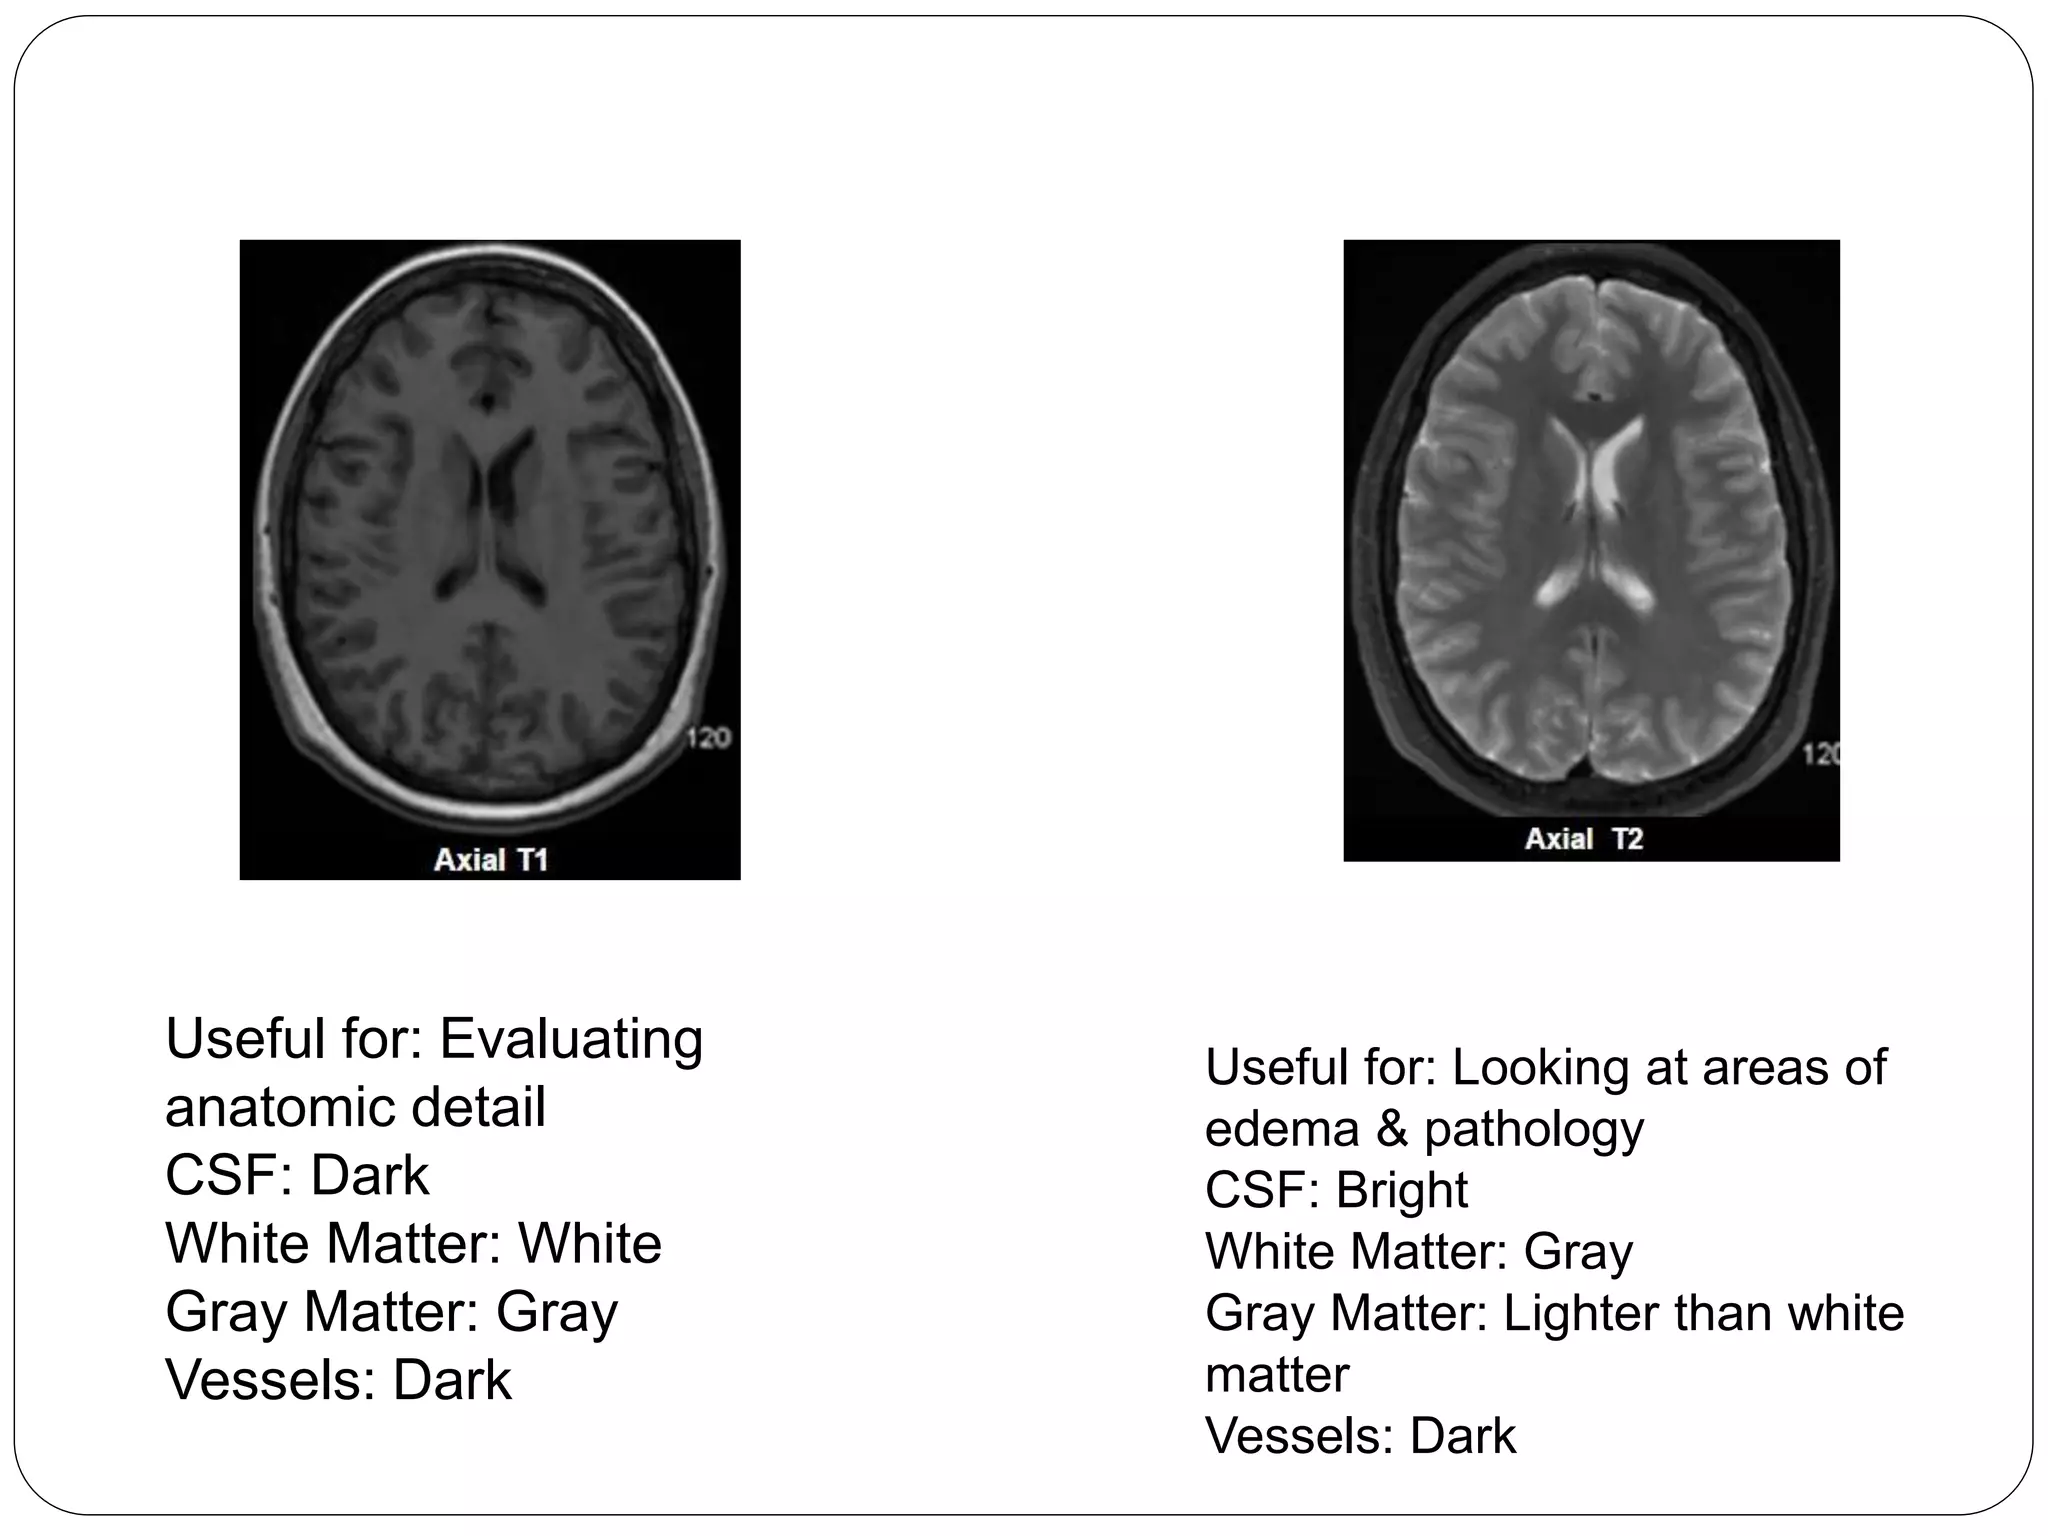

Types of MR Images

Useful for: Evaluating anatomic

detail

CSF: Dark

White Matter: White

Gray Matter: Gray

Vessels: Dark

Useful for: Evaluating for BBB breakdown

in the setting of tumor, infection, MS etc.

Vessels: Brigh

Useful for: Looking at areas of edema &

pathology

CSF: Bright

White Matter: Gray

Gray Matter: Lighter than white matter

Useful for: Evaluating areas of edema with

CSF subtraction. Edema stands out

because is CSF dark

Useful for: stroke imaging, abscess,

cellular tumors

Fuzzier image than FLAIR

T2* (T2-star, or SWI)

Form of T2-weighted image which is

susceptible to iron or calcium

Blood, bone, calcium appear dark

Area of blood often appears much larger

than reality(“blooming”)

Useful for: Identification of early

hemorrhage

Look for: DARK only

Recognition:

o Like T2 except

o Cranium, scalp are dark or absent

o Dark areas near frontal and temporal